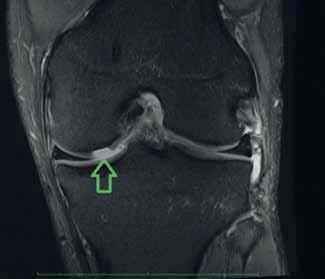

Rycina 4.1. Podchrzęstne ognisko obrzęku szpiku w zakresie kłykcia bocznego kości udowej (strzałki)

Rycina 4.2. Hiperintensywny obszar uszkodzenia chrząstki stawowej w zakresie MFC – kłykcia przyśrodkowego k. udowej (strzałka)